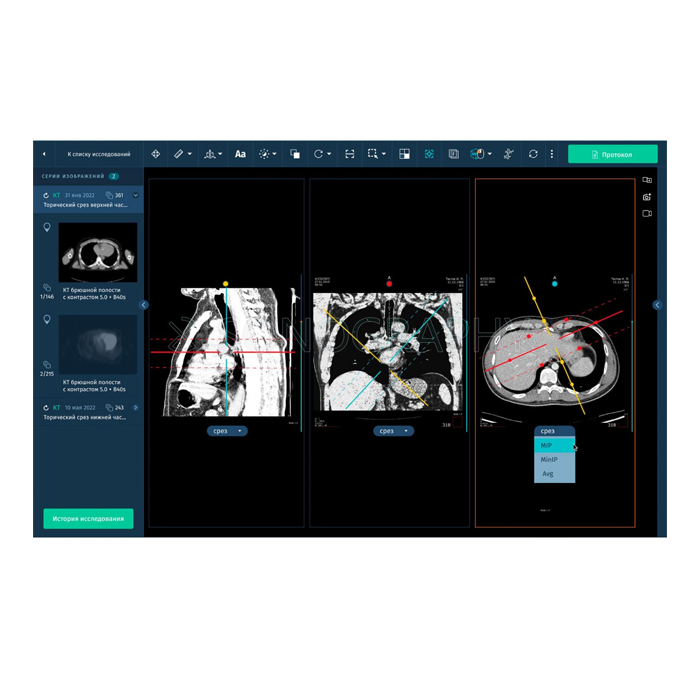

АрхиМед PACS/RIS — это комплексное программное решение для цифровизации и оптимизации работы лучевой диагностики. Система объединяет процессы управления исследованиями (RIS), хранения и обработки медицинских изображений (PACS), а также создания структурированных отчетов. Это фундамент для создания современного, эффективного и безопасного радиологического отделения или целой сети медицинских учреждений.

Внедрение системы АрхиМед PACS/RIS позволяет перевести диагностический процесс на качественно новый уровень: от момента назначения исследования до архивирования его результатов, обеспечивая врачам удобные инструменты для анализа, а пациентам — скорость и точность диагностики.

- Работа с изображениями: Автоматический прием снимков с любого DICOM-совместимого оборудования (КТ, МРТ, рентген, УЗИ и др.), организация единого защищенного архива.

- Описание и отчетность: Удобные рабочие станции для врачей-рентгенологов с шаблонами протоколов, голосовым вводом и поддержкой нормативных форм.

- Повышение качества диагностики: Доступ к полной истории изображений пациента, инструменты для сравнения, точных измерений и постобработки.

| Клиентская часть | Толстый клиент (рабочая станция), Веб-клиент, Мобильный доступ |